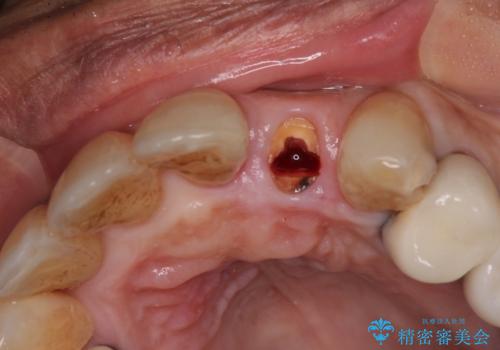

診察をしたところ、歯根に縦破折が認められ、抜歯が必要と判断されました。

抜歯、インプラント埋入、仮歯の装着が同時に可能な1DAYインプラントが適用可能と判断されたため、インプラントによる補綴治療を行うこととしました。